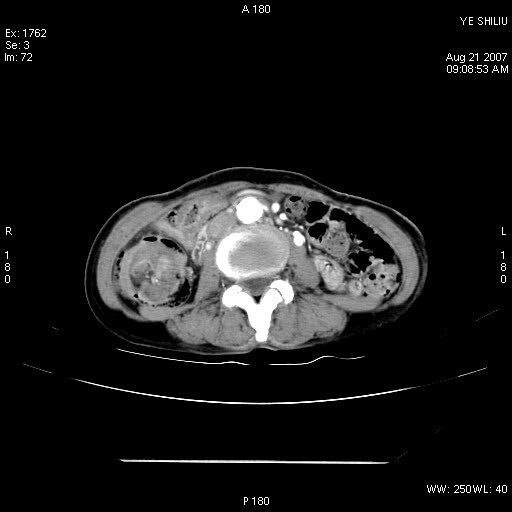

回盲部腺癌

患者,女,74岁,腹痛一周。开始为脐周疼痛,后转移至右下腹。治疗经过:门诊拟急性阑尾炎收内科治疗,b超示胆囊结石、胆囊炎转外科。拟行胆囊切除术前检查ct。